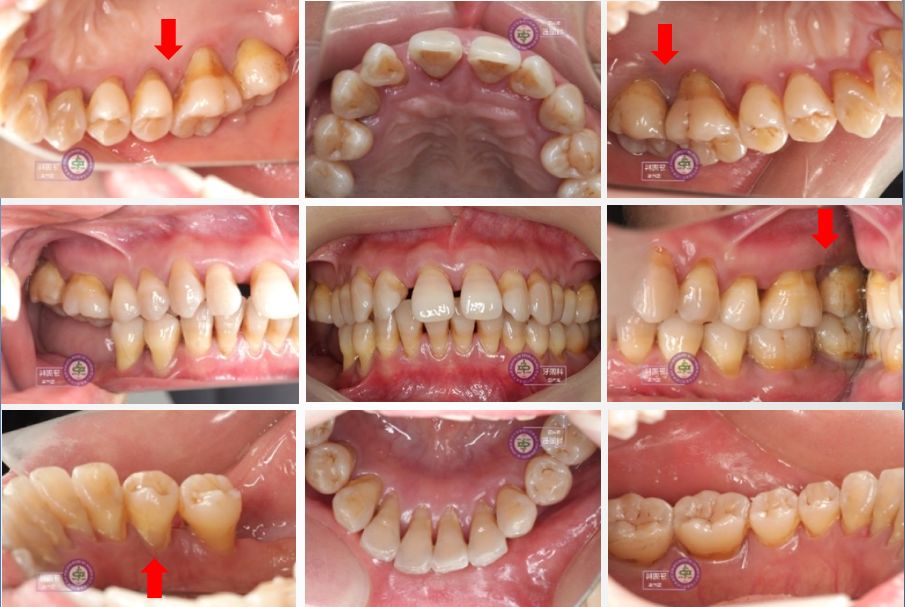

患者治疗前口内照

患者基础治疗一年半后口内照